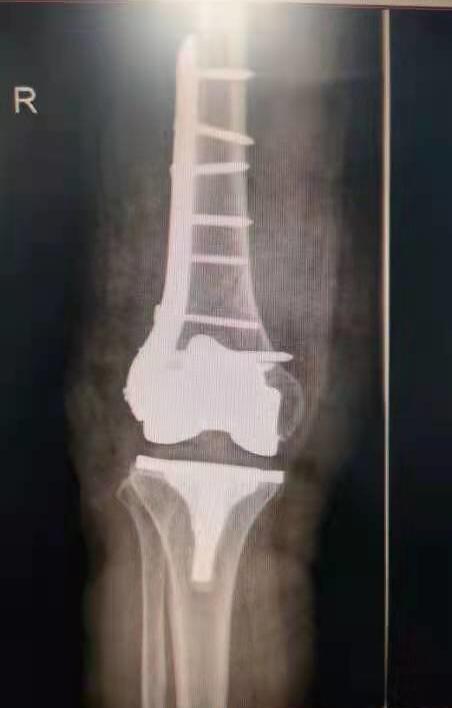

手術(shù)后照片

12月7日,在醫(yī)護(hù)團(tuán)隊(duì)的默契合作下,歷時(shí)1個(gè)多小時(shí),吳阿姨的手術(shù)順利完成。經(jīng)過(guò)兩周的后續(xù)治療,吳阿姨已經(jīng)可以站起來(lái),借助拐杖行走。“醫(yī)生們這次又讓我站起來(lái)了。”吳阿姨開(kāi)心地說(shuō)。

“關(guān)節(jié)假體需要進(jìn)行‘翻修’固定,要保證骨折部位修復(fù)后假體的穩(wěn)定性,還要考慮患者年齡大,曾接受過(guò)多次手術(shù),患有多種基礎(chǔ)疾病,手術(shù)技術(shù)難度高,對(duì)醫(yī)生和患者都是一次挑戰(zhàn)?!弊鳛槭中g(shù)團(tuán)隊(duì)成員和吳阿姨主管醫(yī)生的王旌晶覺(jué)得一定要對(duì)得起患者及家屬這份沉甸甸的信任。

“隨著骨科關(guān)節(jié)置換技術(shù)的飛速發(fā)展,老年髖關(guān)節(jié)假體和膝關(guān)節(jié)假體周?chē)钦鄣幕颊邤?shù)量不斷增加,這類(lèi)患者往往合并有多種基礎(chǔ)疾病,手術(shù)難度更高,各種要求也更高。” 王旌晶說(shuō),醫(yī)院骨傷三科在李彬主任的帶領(lǐng)下,經(jīng)過(guò)多年對(duì)老年人骨折處理的經(jīng)驗(yàn)總結(jié),對(duì)于這類(lèi)患者還是有相當(dāng)豐富的手術(shù)經(jīng)驗(yàn)和技巧,“假體周?chē)钦凼中g(shù)”開(kāi)展后大大降低了老年人此類(lèi)骨折后并發(fā)癥的發(fā)生,明顯改善患者的生活質(zhì)量,“解放了”患者家屬。